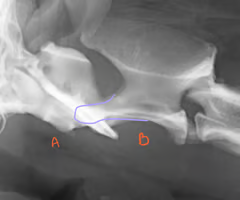

Identify the structures?

A: Atlas C1

B: Axis C2

Purple: dens

What does the dens allow for?

rotation of head

What may need to be done to see the Dens if it is superimposed w/ the atlas wings ?

Rotate the head